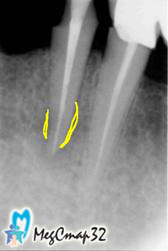

Действие препарата проверялось контрольными снимками (сн.№5 сн.№6)

с интервалами 5 и 7 дней и оценивалось улучшение состояние зуба.

После полного рассасывания препарата за верхушкой корня зуба,

канал был окончательно запломбирован с использованием гуттаперчи

и восстановлен светоотверждаемым материалом (сн№7).

Контрольный снимок (сн№8),

сделанный через неделю показал

исключительно благоприятный исход лечения.

Особо следует отметить, что прежний протез был установлен на свое место.

Контрольный снимок, сделанный через полгода (сн.№9)

подтверждение успеха лечения:

полное восстановление костной ткани около корня и отсутствие воспаления,

т.е. результат, превзошел все ожидания.